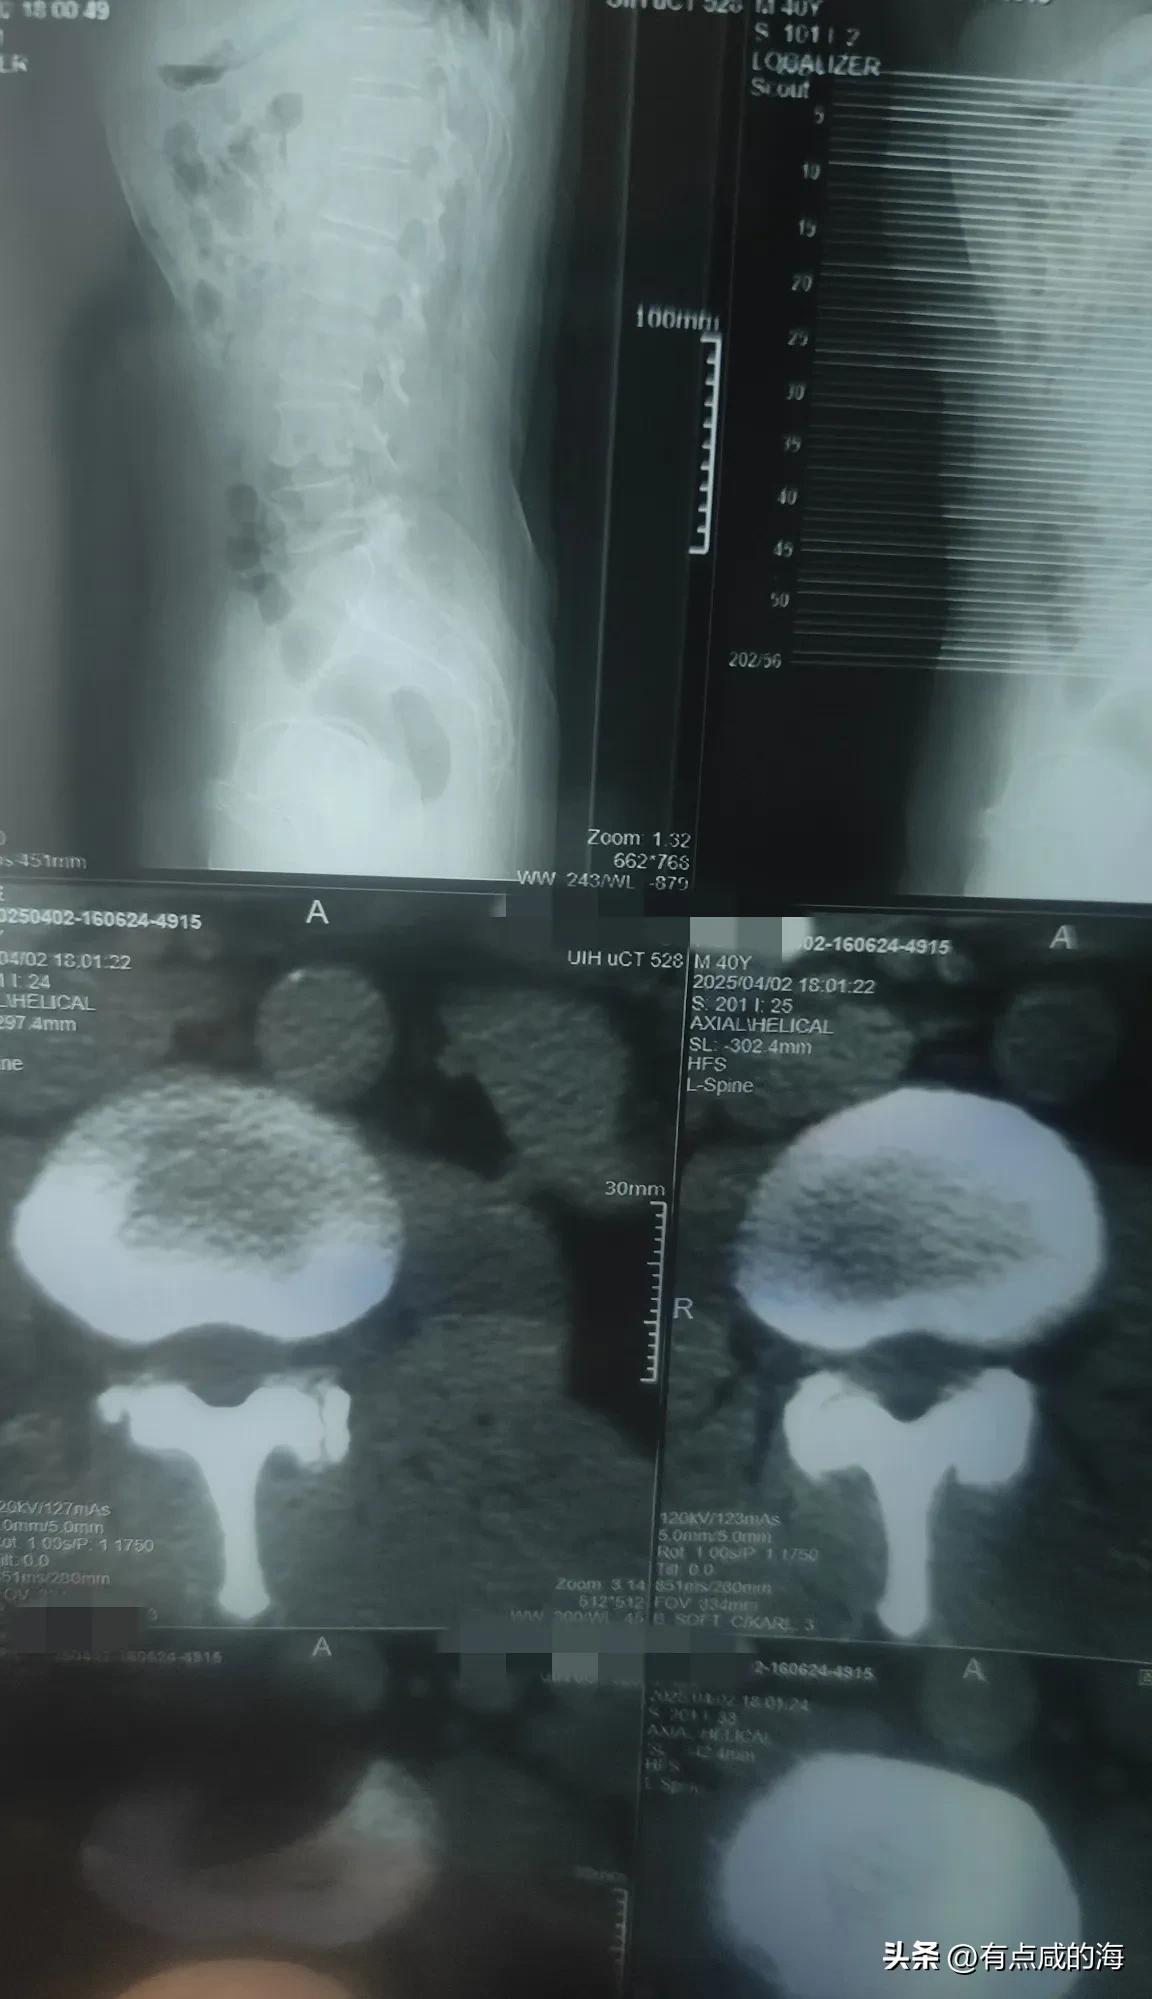

哪位大哥大姐给看看片子,刚拍的 说有点腰间盘突出,还说有个肾结石,花生米大小,现在报告还没有出,医生下班,这两天腰有点难受,不是疼,自己老感觉是受凉了,但就是会不自觉的疼一下,好像是酸一下无力,各位大神有什么办法给出出主意吧?真的有点难受,就是和正常身体有不一样的感觉,腰椎间盘突出 肾结石 腰椎间盘突出症 腰间盘突出 腰突间盘 腰槯间盘突出 腰腰椎疼痛